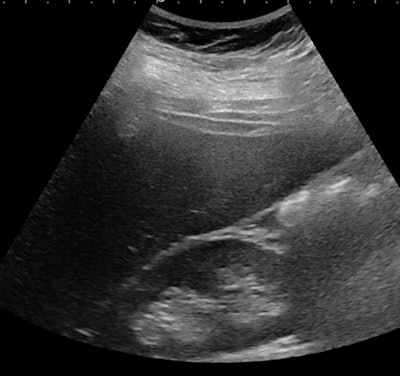

![Ultrasound of a 14-year-old girl with severe obesity (body mass index [BMI], 42 kg/m2). There is hepatomegaly associated with increased liver echogenicity when compared to the right kidney and attenuation corresponding to severe steatosis. Below, the same patient shows increased liver-to-kidney ratio. All images courtesy of Dr. Stéphanie Franchi-Abella, PhD.](https://img.auntminnieeurope.com/files/base/smg/all/image/2019/10/ame.2019_10_10_21_09_1189_steatose-fig-1a.png?auto=format%2Ccompress&fit=max&q=70&w=400)

Early detection is important, as diet may reverse the process at the early phase of the disease. Yet the detection and quantification of liver fat content and associated fibrosis and inflammation, mandatory in the diagnosis of NASH, remain challenging in children; B-mode ultrasound remains relatively limited for the diagnosis of liver steatosis, as fat content should be more than 20%, but quantification is not yet available as a routine clinical tool on ultrasound scanners, according to Franchi-Abella.